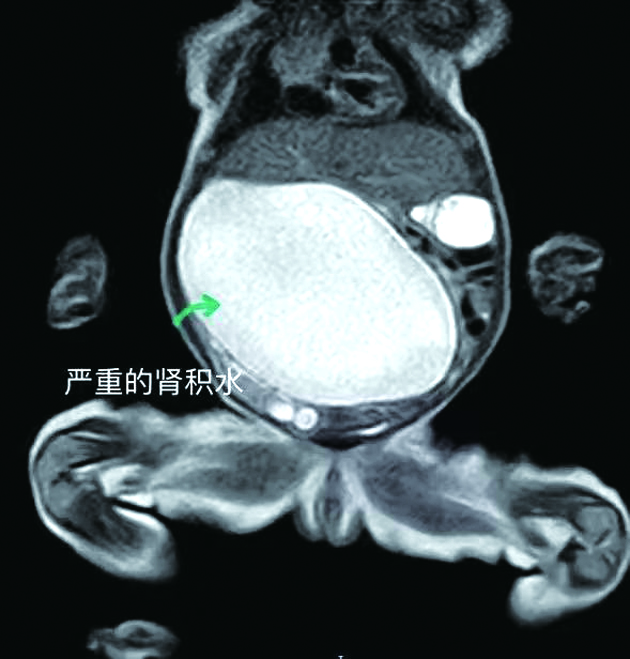

小花的影像学检查结果。医院供图

比常人多一个肾可不是什么好事。小花出生后没多久,右肾的积水越来越严重,但当地医院对小花的情况束手无策。于是,小花的家长把她转院到柳州市妇幼保健院治疗。

入院后,柳州市妇幼保健院小儿外科的医护人员对小花悉心照顾,通过造瘘管将其肾积水引流排出,定期随访,等待最佳的手术时机。